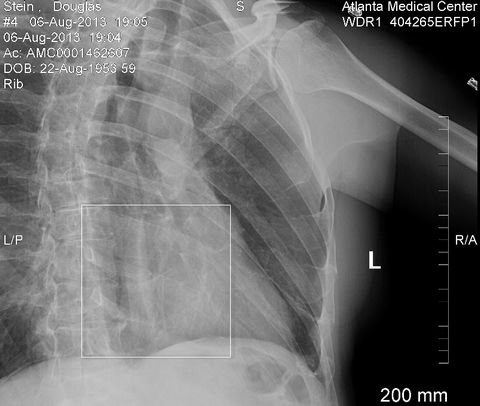

Any movement was painful, but this was exaggerated by the

When not out of alignment, rib fractures can be difficult to

find, but this one seems rather obvious.![]() |